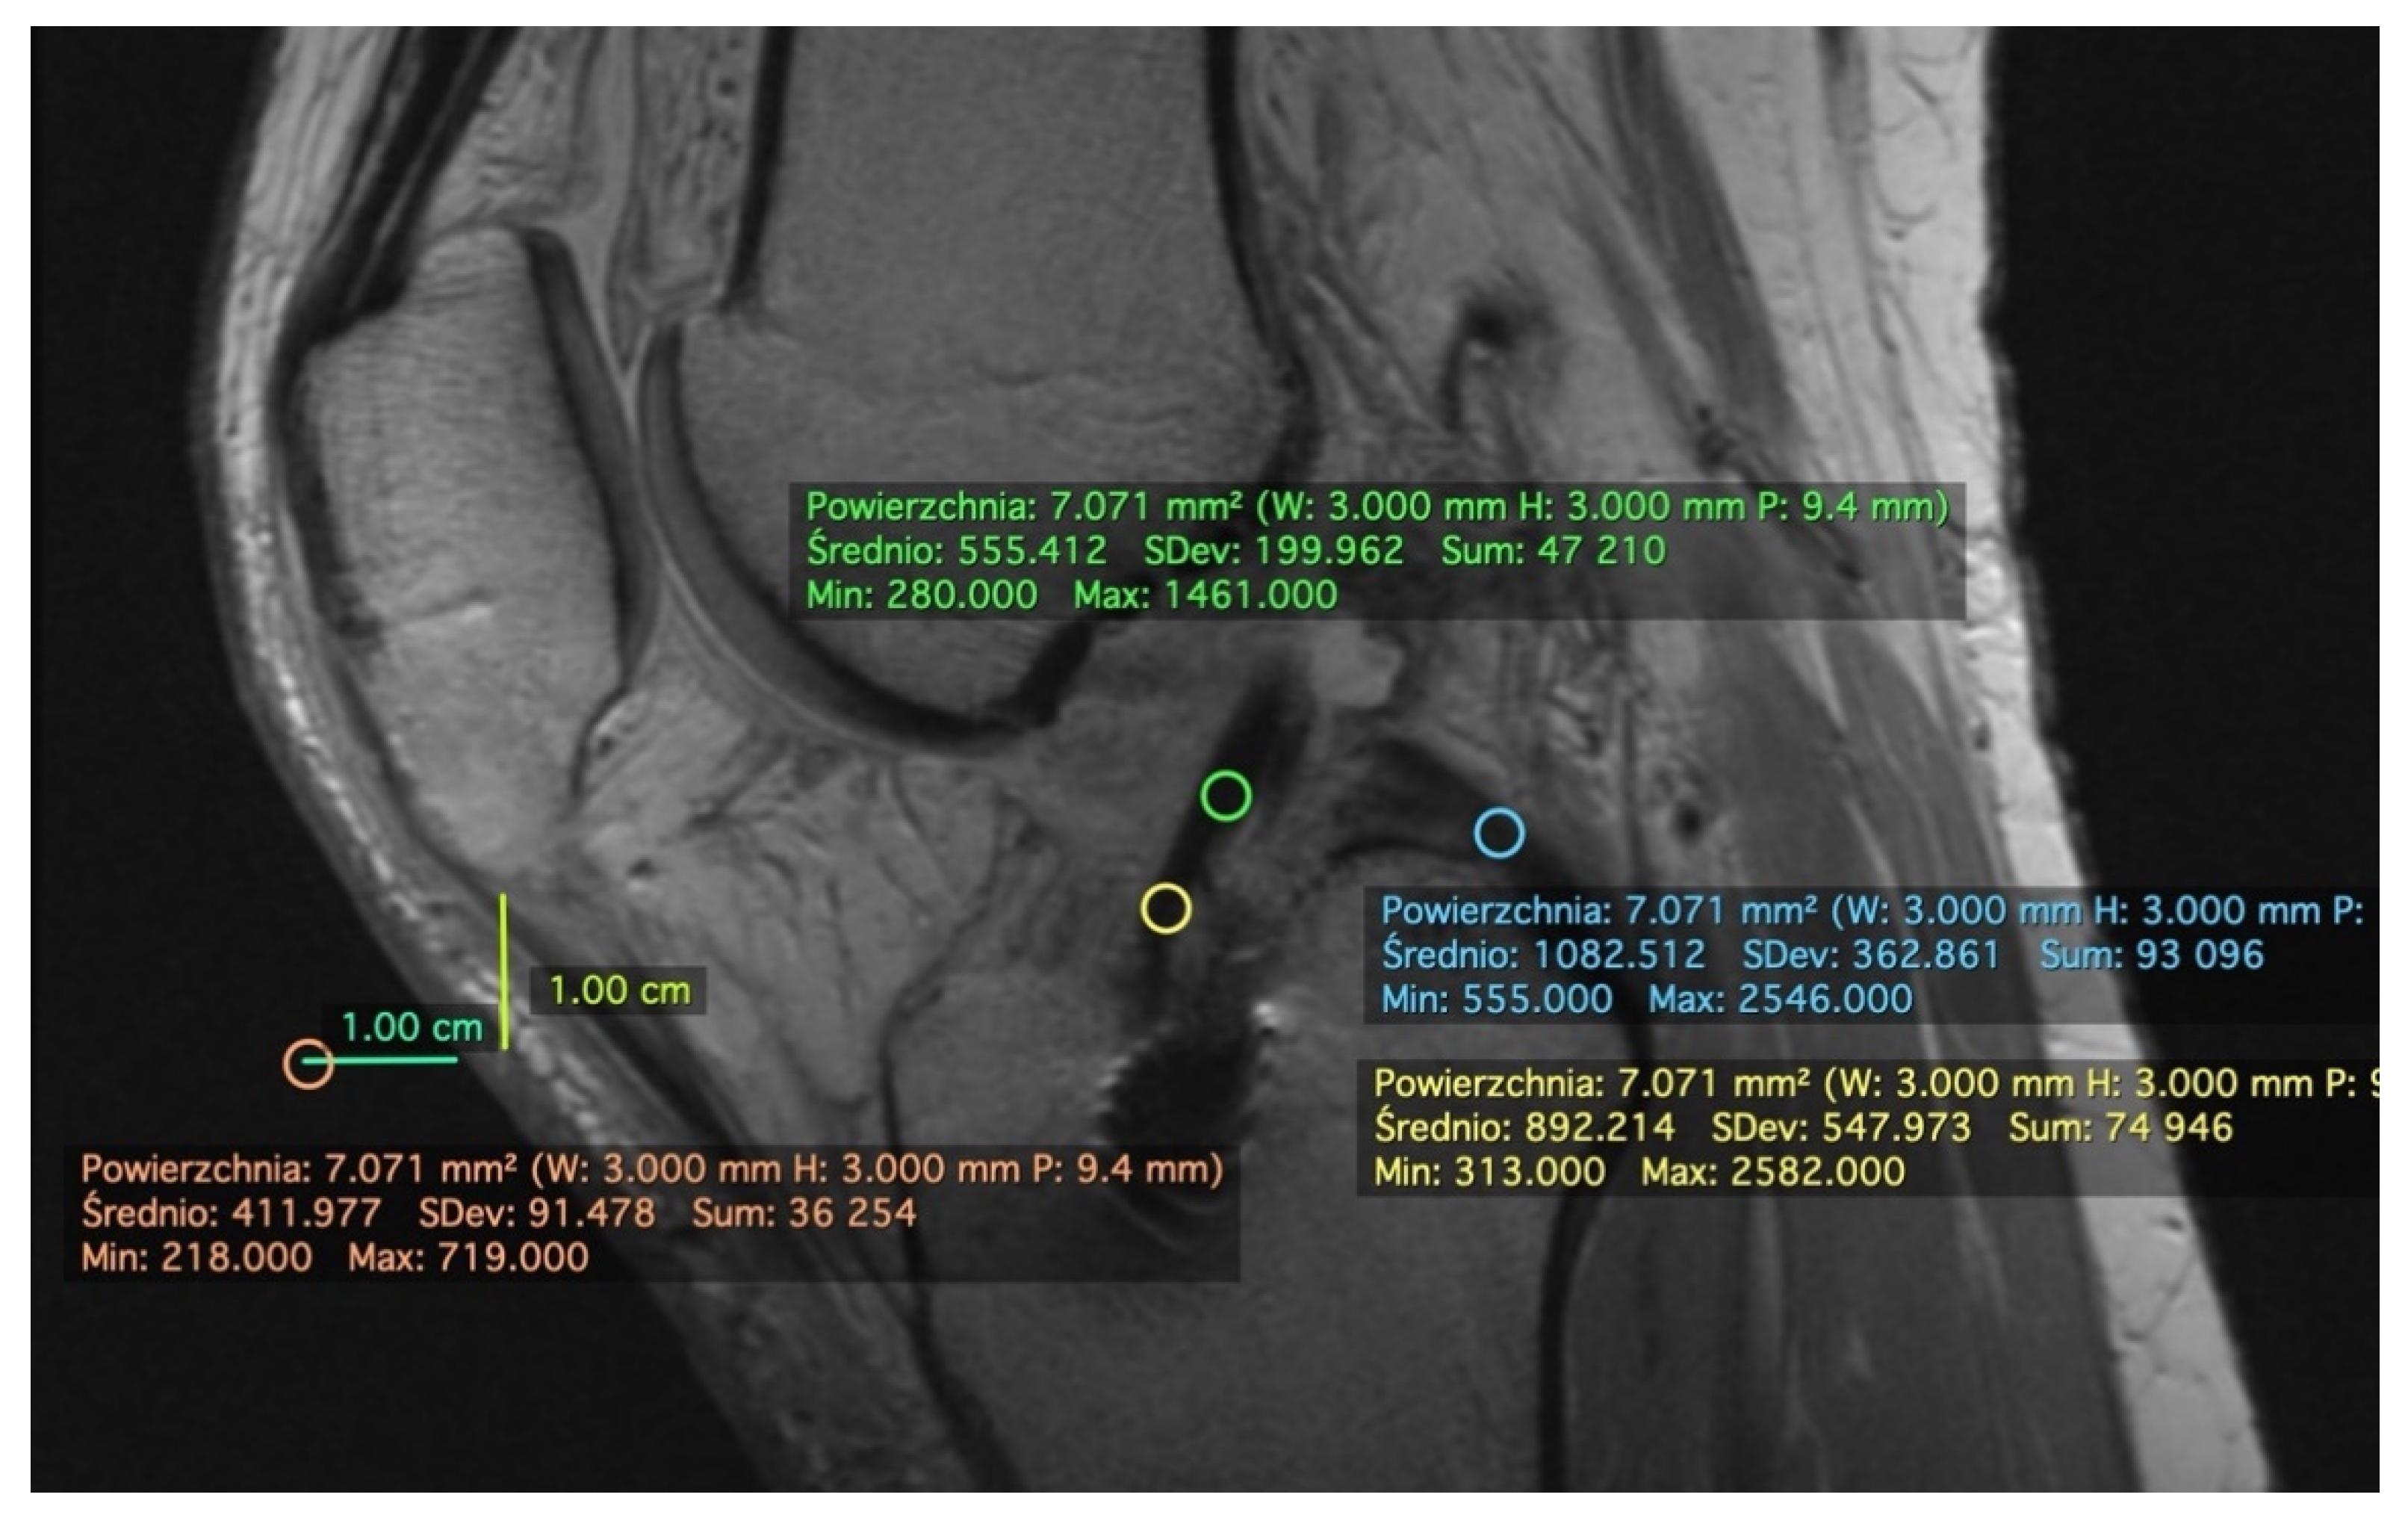

2.1. Measurement on the Sagittal Plane

2.2. Measurement on the Axial Plane